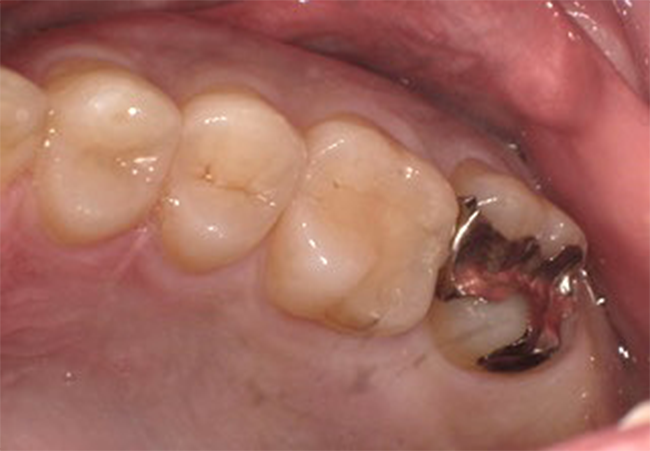

Before②

年齢・性別

29歳男性

主訴

銀歯を換えたい

診査診断

審美障害

治療計画

セレックによるセラミック治療

治療期間・金額

1日2回 ¥33,000

リスク

知覚過敏、歯ぎしり等による破折